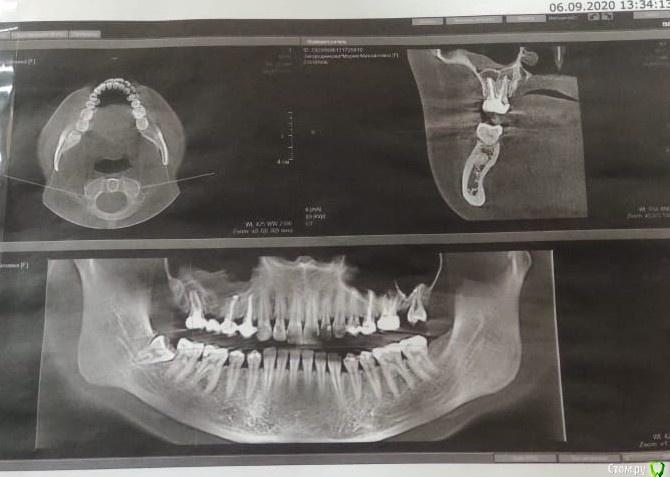

Добрый день! Обращаюсь к Вам за помощью, так как мнения врачей разделились, а я уже и не знаю, что думать. Над 5-м зубом возник свищ, сейчас он есть уже на протяжении 3-х месяцев, началось с того, что летом был гайморит и было сильное давление на область зубов (там, где установлен мост), в итоге, пила антибиотики и в целом состояние улучшилось. При этом не проходило ощущение давления в пазухе, стоматолог предложила проставить в десну линкомицин, дабы воспаление уменьшилось, после проставленных уколов, образовался свищ, тяжесть в пазухе так же присутствует. Стоматолог-терапевт говорит подождать, может, пройдет. Хирург говорит удалять 5 и 7, ставить имплантаты. Прилагаю снимок и прошу вашей помощи. Что же делать в данной ситуации? Есть ли шанс на то, что зуб можно сохранить? Может, стоит сделать резекцию верхушки?

Один снимок до мостовидного протеза (2019 год), второй сентябрь 2020.

Зуб 17, по моему мнению, придётся удалить; про 15 недостаточно информации. Неплохо бы свежую комп. томографию посмотреть (хотя бы от 09.2020), а не снимки скришотов с монитора. Постарайтесь выложить. Инструкция, как это сделать в самом начале пациентского раздела.